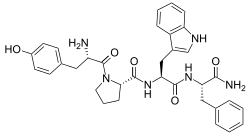

Opioid peptides

Endomorphins

Endorphins

Structures

Enkephalins

Structures

| Enkephalins | ||||

|---|---|---|---|---|

DAMGO DAMGO |

||||

Propeptides

Others / unknown

- Adrenorphin

- Amidorphin

- Biphalin

- Casokefamide

- Casomorphins

- Cytochrophin-4

- DALDA (Tyr-D-Arg-Phe-Lys-NH2)

- Deltorphin I

- Deltorphin II

- Deprolorphin

- Dermorphin

- DPDPE

- Frakefamide

- Gliadorphin

- Gluten exorphins

- Hemorphin-4

- Metkefamide

- Morphiceptin

- Nociceptin

- Octreotide

- Opiorphin

- Rubiscolin

- Soymorphins

- Spinorphin

- TRIMU 5

- Tynorphin

- Valorphin

- Zyklophin

Structures

| Other or unknown opioid peptides | ||||

|---|---|---|---|---|

Adrenorphin Adrenorphin |

Amidorphin Amidorphin |

Casomorphin Casomorphin |

DALDA DALDA |

|

DPDPE DPDPE |

Endomorphin-1 Endomorphin-1 Endomorphin-2 Endomorphin-2 |

Gliadorphin Gliadorphin |

Morphiceptin Morphiceptin | |

Nociceptin Nociceptin |

Octreotide Octreotide |

Opiorphin Opiorphin |

Rubiscolin Rubiscolin |

TRIMU 5 TRIMU 5 |